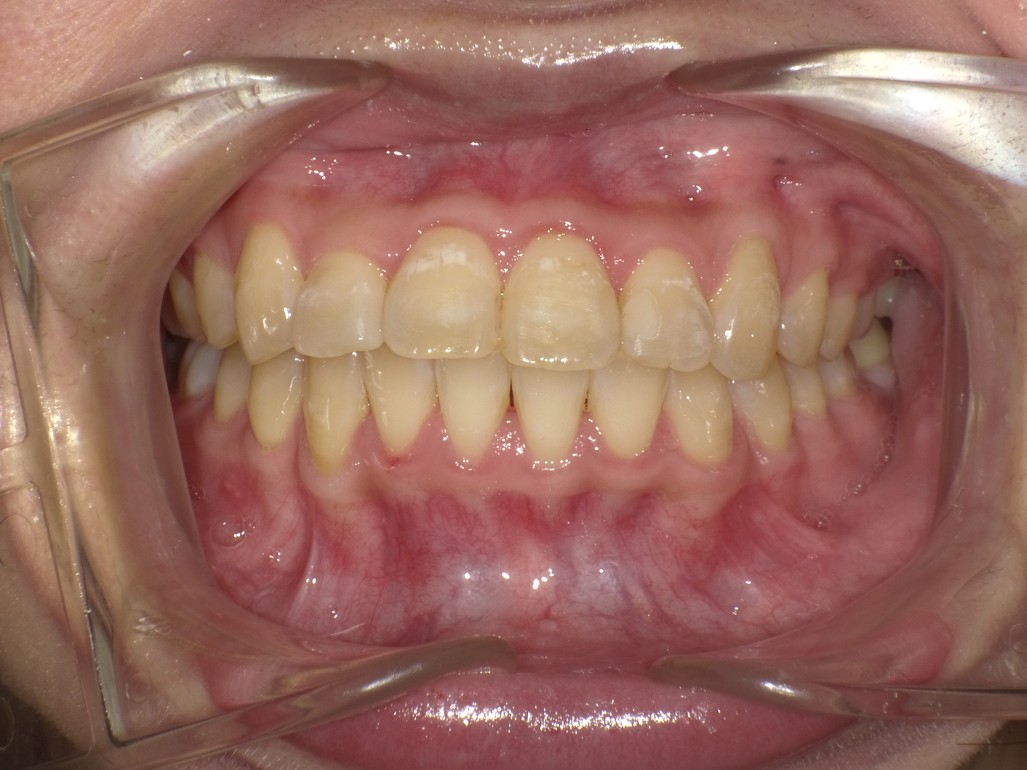

叢生を改善した1症例

治療後 ![]() |

術後経過/現在の状態 |

予後良好 |

クリニックより |

アライナー矯正で8ヶ月ほど、ワイヤー矯正で4ヶ月ほど治療を行なっています。 |